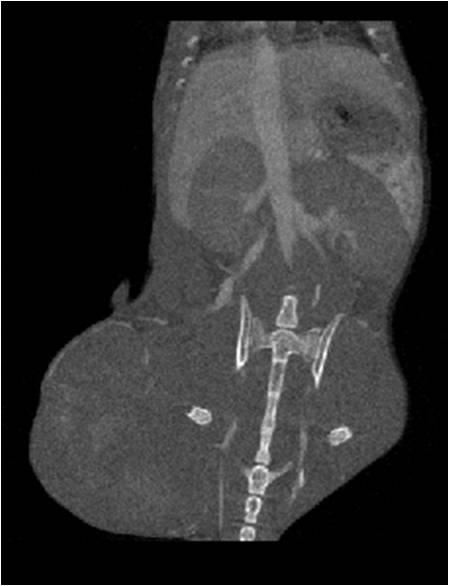

無(wú)造影劑注入                                     造影劑注入

心血管

胸部和心血管的層析成像                                       胸部和心血管的3D圖像

心血管.jpg     心血管1.jpg